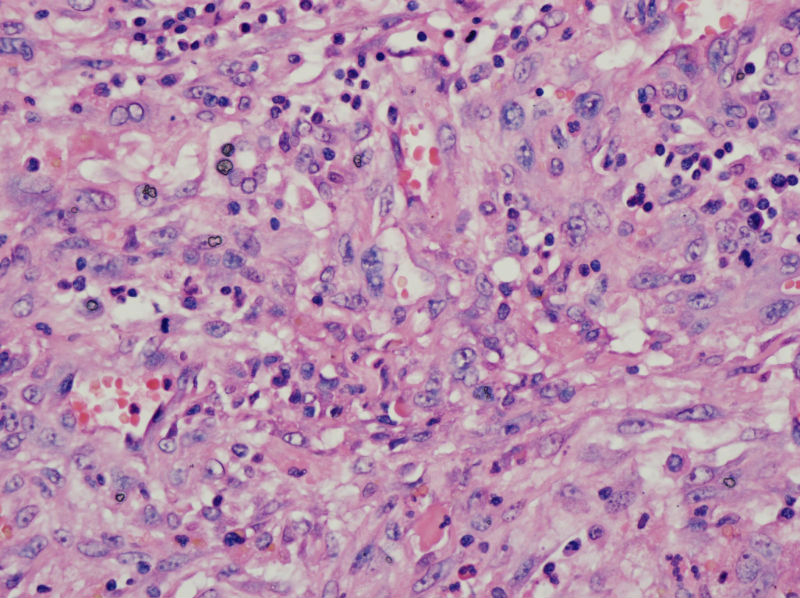

男,44,甲状腺囊肿.直径1.5公分,内流清亮液

结节性甲状腺肿伴出血、囊性变。囊肿边上的滤泡大小不一,纤维组织增生,还可见炎细胞浸润。

结节性甲状腺肿伴囊性变。图2右上角的滤泡上皮似乎有些嗜酸性变。总之:良性病变。图13伴有出血。

补充,,包膜不完整..囊内壁就是图2,图3..